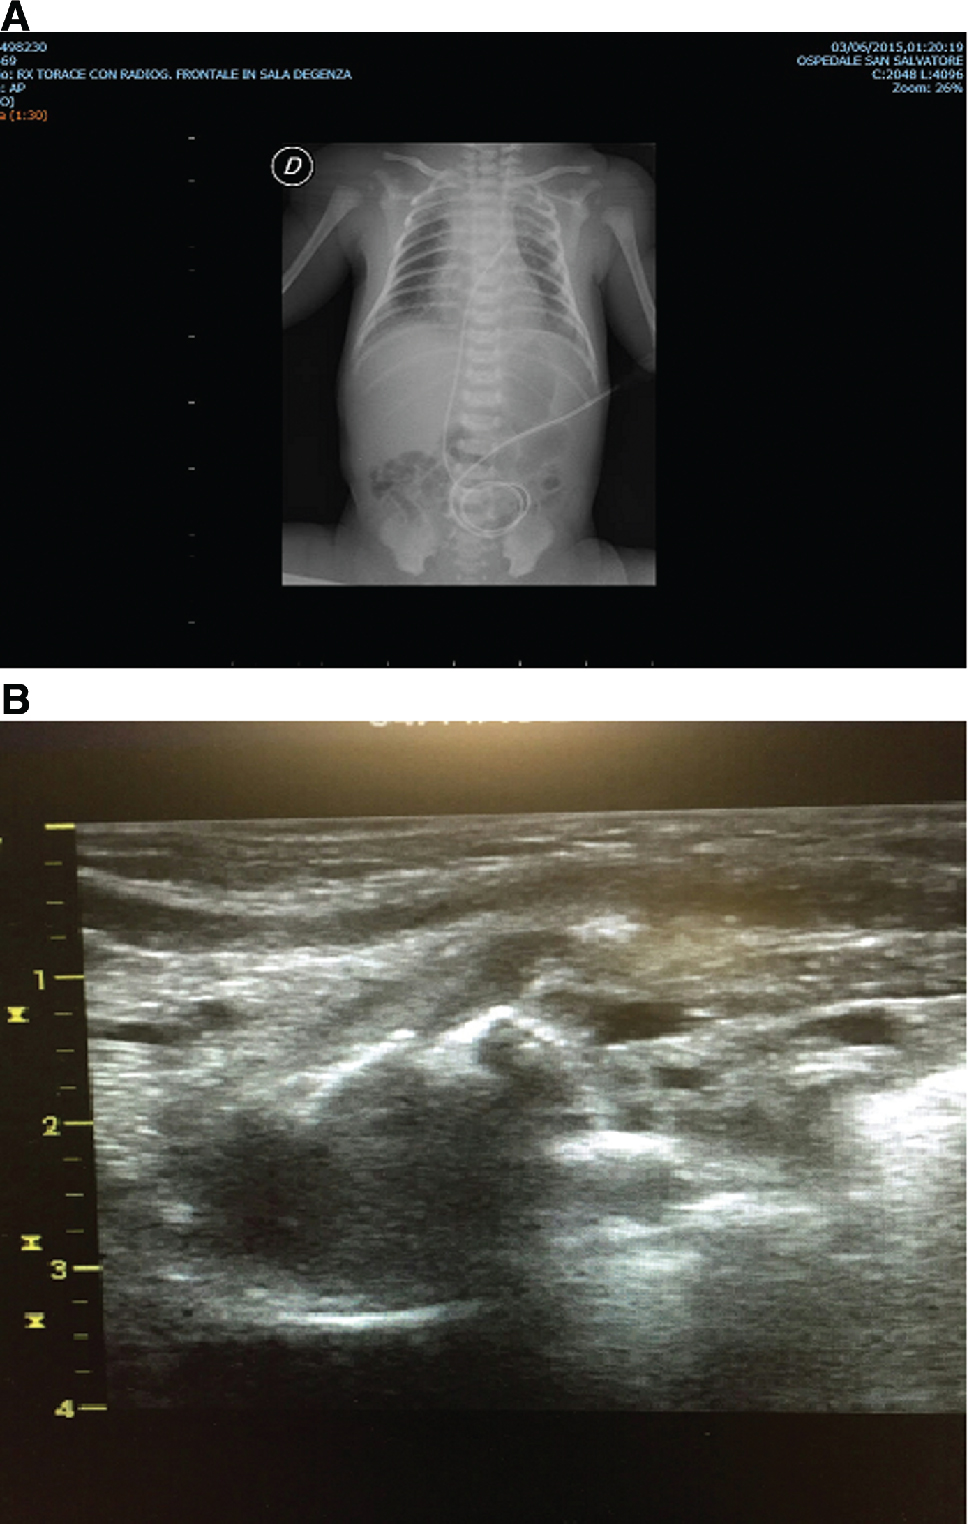

K.R., a male was born at 36 + 4 weeks of gestational age (GA), by an emergency cesarean section (CS) due to maternal pre-eclampsia (birth weight 3100 g, 50th percentile). He was admitted to our NICU soon after birth for respiratory distress syndrome (RDS), needing nCPAP support (CPAP 5.5 cm H2O, FiO2 0.25). CXR on admission revealed a pneumomediastinum and a radiolucent area, likely a pneumatocele in the middle-basal right lung (Figure 1A). The LUS revealed a characteristic picture of an intrapulmonary multilobed cyst, below the pleural line, with a thin hyperechoic external wall and a hypohecoic centrum (Figure 1B). Due to the clinical stability of the patient, sequential LUS were performed instead of CXR. nCPAP was discontinued on day 5 without the need for supplementary respiratory support. LUS revealed a progressive reduction in the cyst’s size, with a complete resolution on day 14. CXR performed at discharge, revealed a minimal residual lesion. The infant was discharged on day 16. Due to the clinical stability and no need of respiratory support, the CT scan was not performed. Monthly CXR was then performed, until complete resolution of the lesion at 3 months after birth. We performed a follow-up of the patients until 9 months after birth. The infant showed an adequate growth [weight at the last check: 8500 g (25–50th percentile), length (L 71 cm (25–50th percentile), chest circumference (CC) 45.5 cm (50th percentile)], good respiratory dynamics and no pulmonary infections.

(A) Chest X-ray at the beginning in case 1: radiolucent area susceptible for pneumatocele at medio-basal right lung. (B) LUS at the beginning in case 1: intrapulmonary multilobed cyst below the pleural line with a thin hyperechoic outside wall and a hypoechoic centrum.